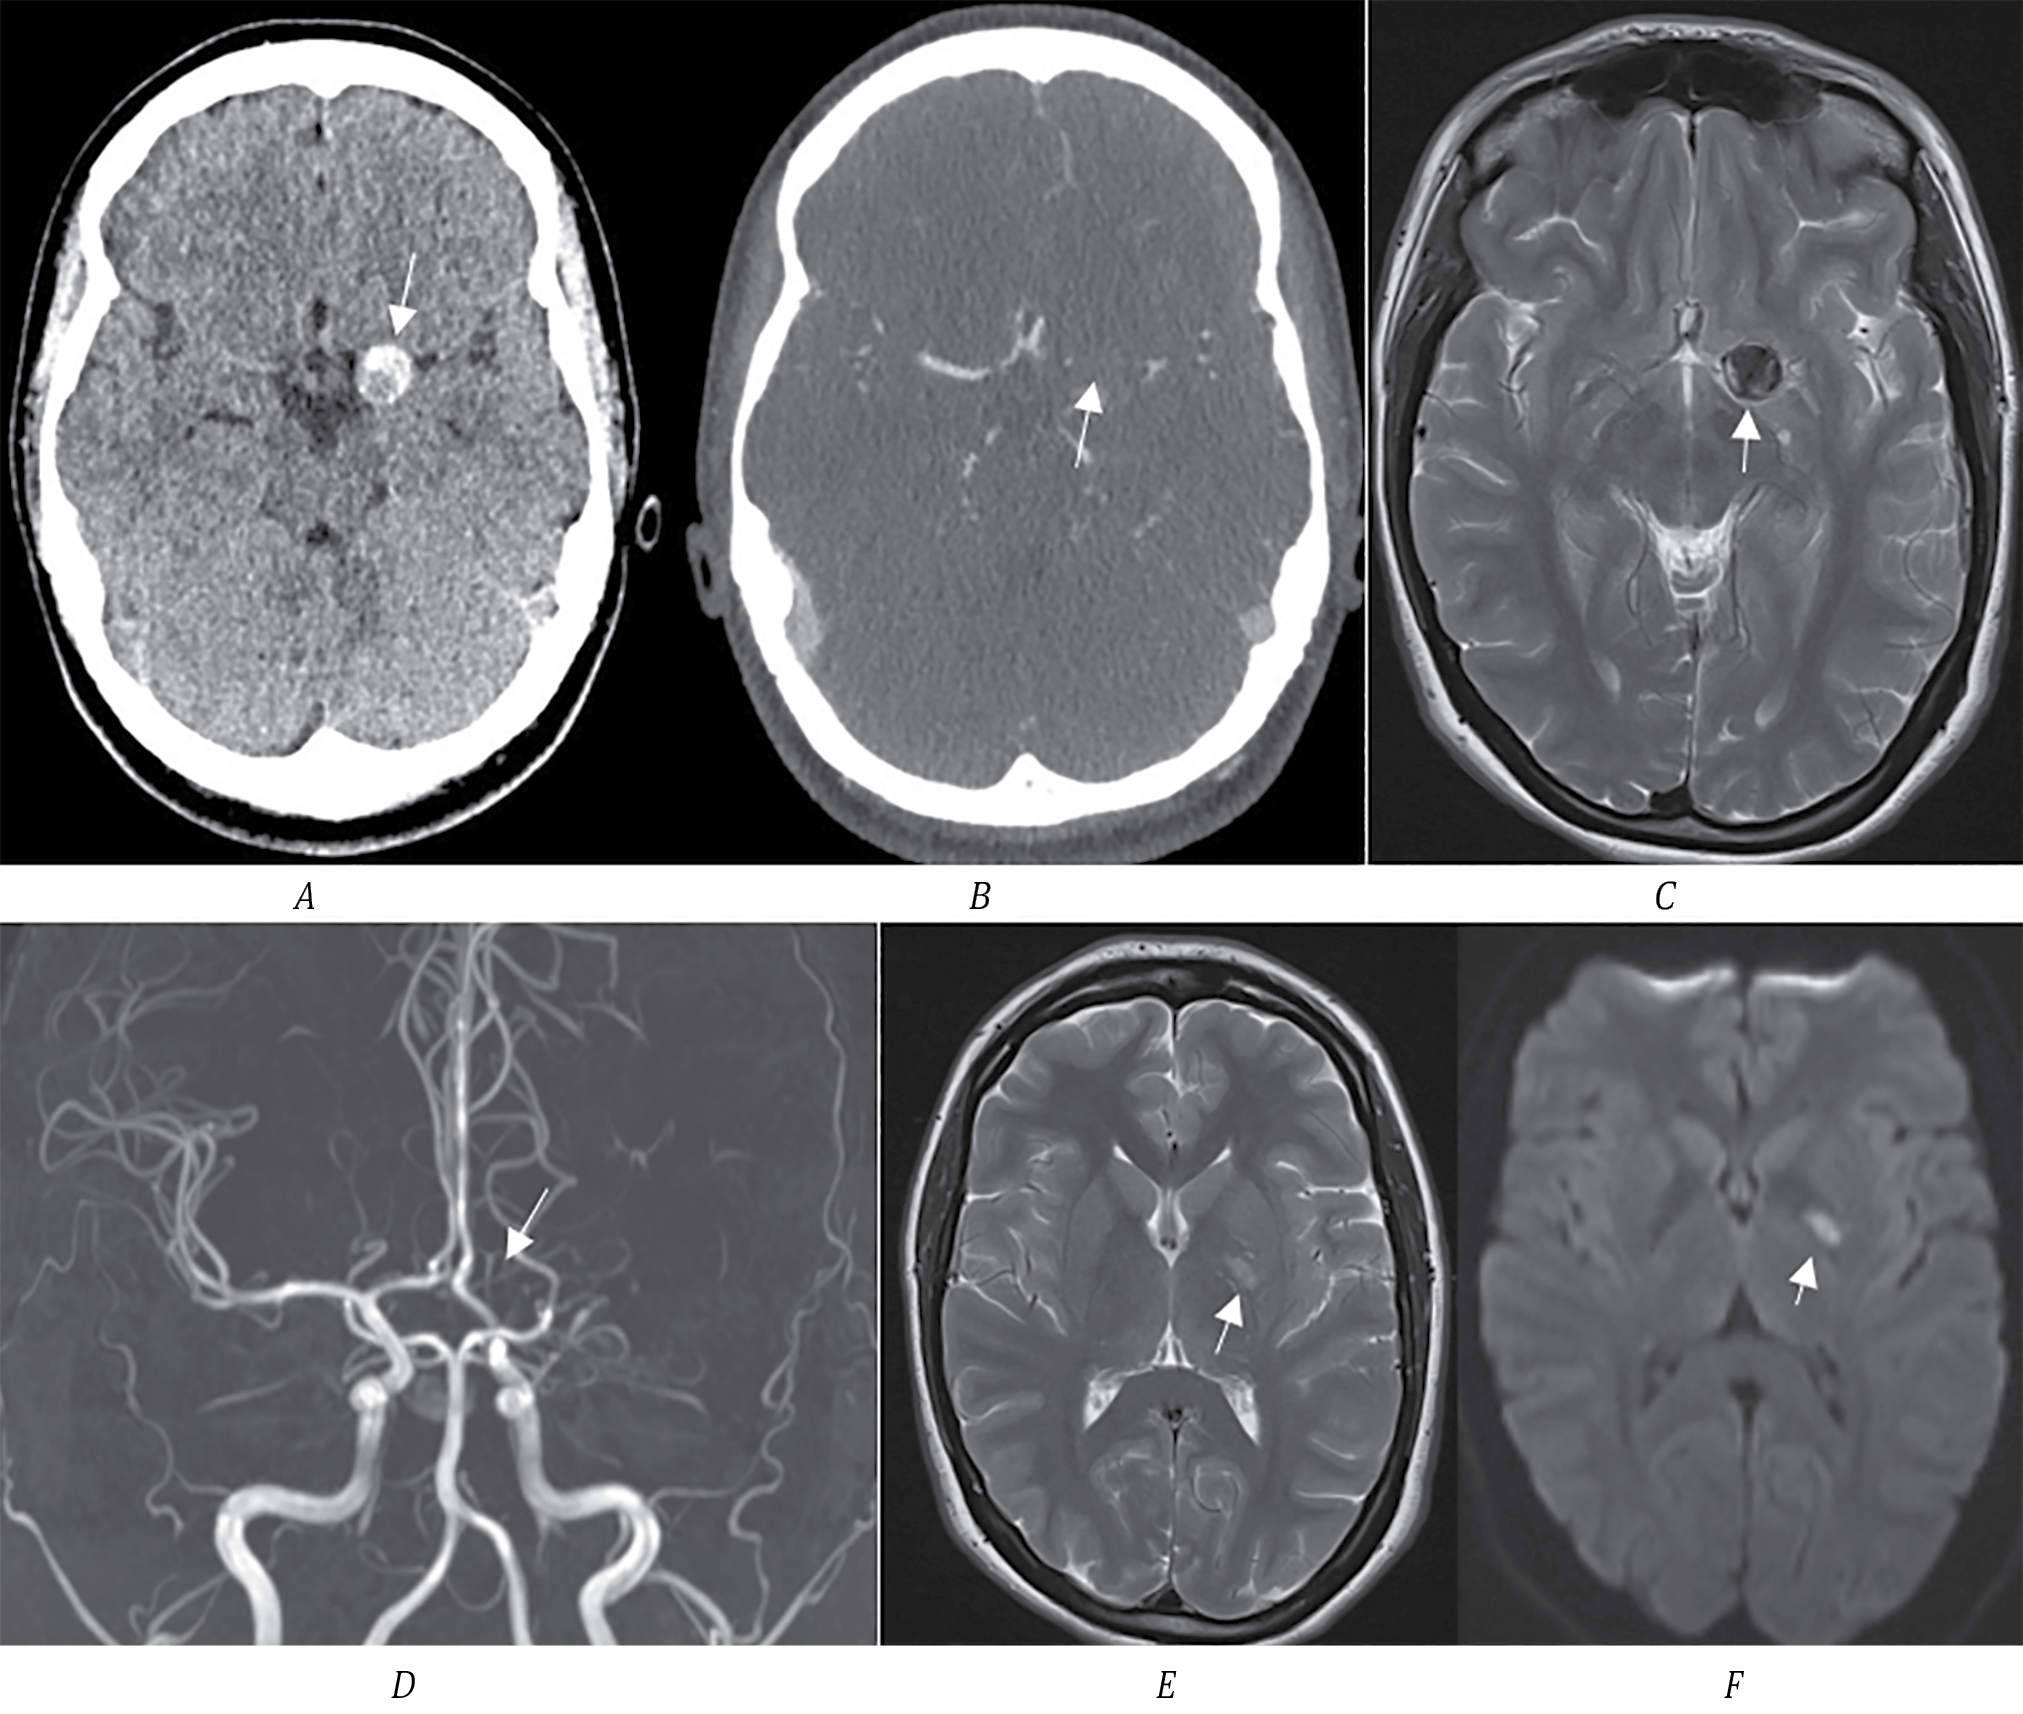

Пациент К., 62 года, поступил в первичное сосудистое отделение с клиникой правостороннего гемипареза (2 балла в руке, 3 — в ноге), моторной афазией, 16 баллов по NIHSS. По МСКТ определяется зона ишемии в левой лобной доле с распространением на подкорковые структуры. По нативному исследованию заподозрена ТА СМА размером до 2 см (рис. 2, А, B). По неясным причинам в первичном сосудистом отделении МСКТ-ангиография не выполнялась. Через 3 мес направлен в региональный сосудистый центр. По МСКТ определяется зона кистозно-атрофических изменений в области перенесённого ИИ в левой лобной доле. По МСКТ-ангиографии определяется небольшая функционирующая часть аневризмы М1-сегмента, дистальные ветви СМА проходимы (рис. 2, C, D).

Рис. 2. МСКТ головного мозга пациента К.

А — МСКТ-натив, определяется зона ишемии в левой лобной доле; B — стрелкой указана ТА СМА с кальцификацией размером до 2 см; C — МСКТ через 3 мес после перенесённого ИИ, определяется зона кистозно-атрофических изменений в левой лобной доле; D — МСКТ-ангиография, белой стрелкой обозначена функционирующая часть аневризмы, чёрной — контур тромбированной части; E — 3D-реконструкция МСКТ-ангиографии, стрелкой указана функционирующая часть аневризмы.

С учётом наличия большого тромбированного мешка аневризмы в области М1-сегмента СМА и развития ишемии в области кровоснабжения лобной М2-ветви СМА вероятна эмболия тромбов из мешка аневризмы. В динамике через 3 мес по ангиографии определяется проходимость всех ветвей СМА, что могло быть связано с наступившей реканализацией тромбированной ветви. При дообследовании других факторов риска ИИ, кроме гипертонической болезни, у пациента не обнаружено. Учитывая высокий риск повторных тромбоэмболических осложнений, выполнили микрохирургическое клипирование аневризмы. После операции состояние пациента декомпенсировалось в связи с развитием энцефалопатии; выписан из стационара с оценкой по модифицированной шкале Рэнкина 4.

Клинический случай 3

Пациентка И., 22 года, доставлена скорой помощью с жалобами на слабость и неловкость в правых конечностях. На момент осмотра — в ясном сознании, правосторонний гемипарез до 3,5 балла в руке, 4 баллов в ноге. По МСКТ определяется округлое образование гиперденсной плотности в проекции сильвиевой щели, подозрение на ТА. Обращает на себя внимание, что образование имеет разную плотность, в том числе участок высокой плотности, как возможный признак острого тромбоза (рис. 3, А). По МСКТ-ангиографии отсутствует кровоток в СМА слева, функционирующей части аневризмы не определяется. Учитывая лёгкий неврологический дефицит (5 баллов по NIHSS), острый тромбоз аневризмы СМА вместе с несущей артерией маловероятен. Пациентке выполнено МРТ головного мозга. Определяется большая ТА СМА, тромбоз СМА на всём протяжении. В области внутренней капсулы определяется участок ишемии, который соответствует развившемуся неврологическому дефициту у пациентки. На основании этого вероятно, что тромбоз аневризмы СМА вместе с артерией является хроническим, а в настоящее время клиническая картина вызвана развитием ишемии в подкорковых структурах, кровоснабжаемых лентикулостриарными артериями. Механизм развития ишемии в данном случае может быть связан как с эмболией тромбами, так и с увеличением размера аневризмы (наличие свежего тромба) и механическим перекрытием артерий.

Рис. 3. МСКТ головного мозга пациентки И.

А — стрелкой обозначена ТА; B — МСКТ-ангиография, белой стрелкой обозначено отсутствие кровотока в левой СМА; C — МРТ Т2-ВИ, стрелкой обозначена ТА СМА; D — МР-ангиография, отсутствие кровотока в СМА слева (указано стрелкой); E, F — МРТ Т2-ВИ и DWI, стрелкой обозначен очаг ишемии в области внутренней капсулы.

Других факторов риска инсульта у молодой пациентки не выявлено. Для определения тактики ведения выполнена церебральная ангиография и МСКТ-перфузия. По данным ангиографии у пациентки хорошо развит коллатеральный кровоток. По данным МСКТ-перфузии значимой разницы капиллярного кровотока в обоих полушариях нет. Принято решение о консервативном ведении пациентки с динамическим ангиографическим контролем. Осмотрена в динамике через 6 мес, повторных эпизодов ишемии у пациентки не было, функциональный статус оценён как 0 баллов по модифицированной шкале Рэнкина. На фоне приёма антиагрегантной терапии по МСКТ-ангиографии признаков реканализации аневризмы и средней мозговой артерии нет.